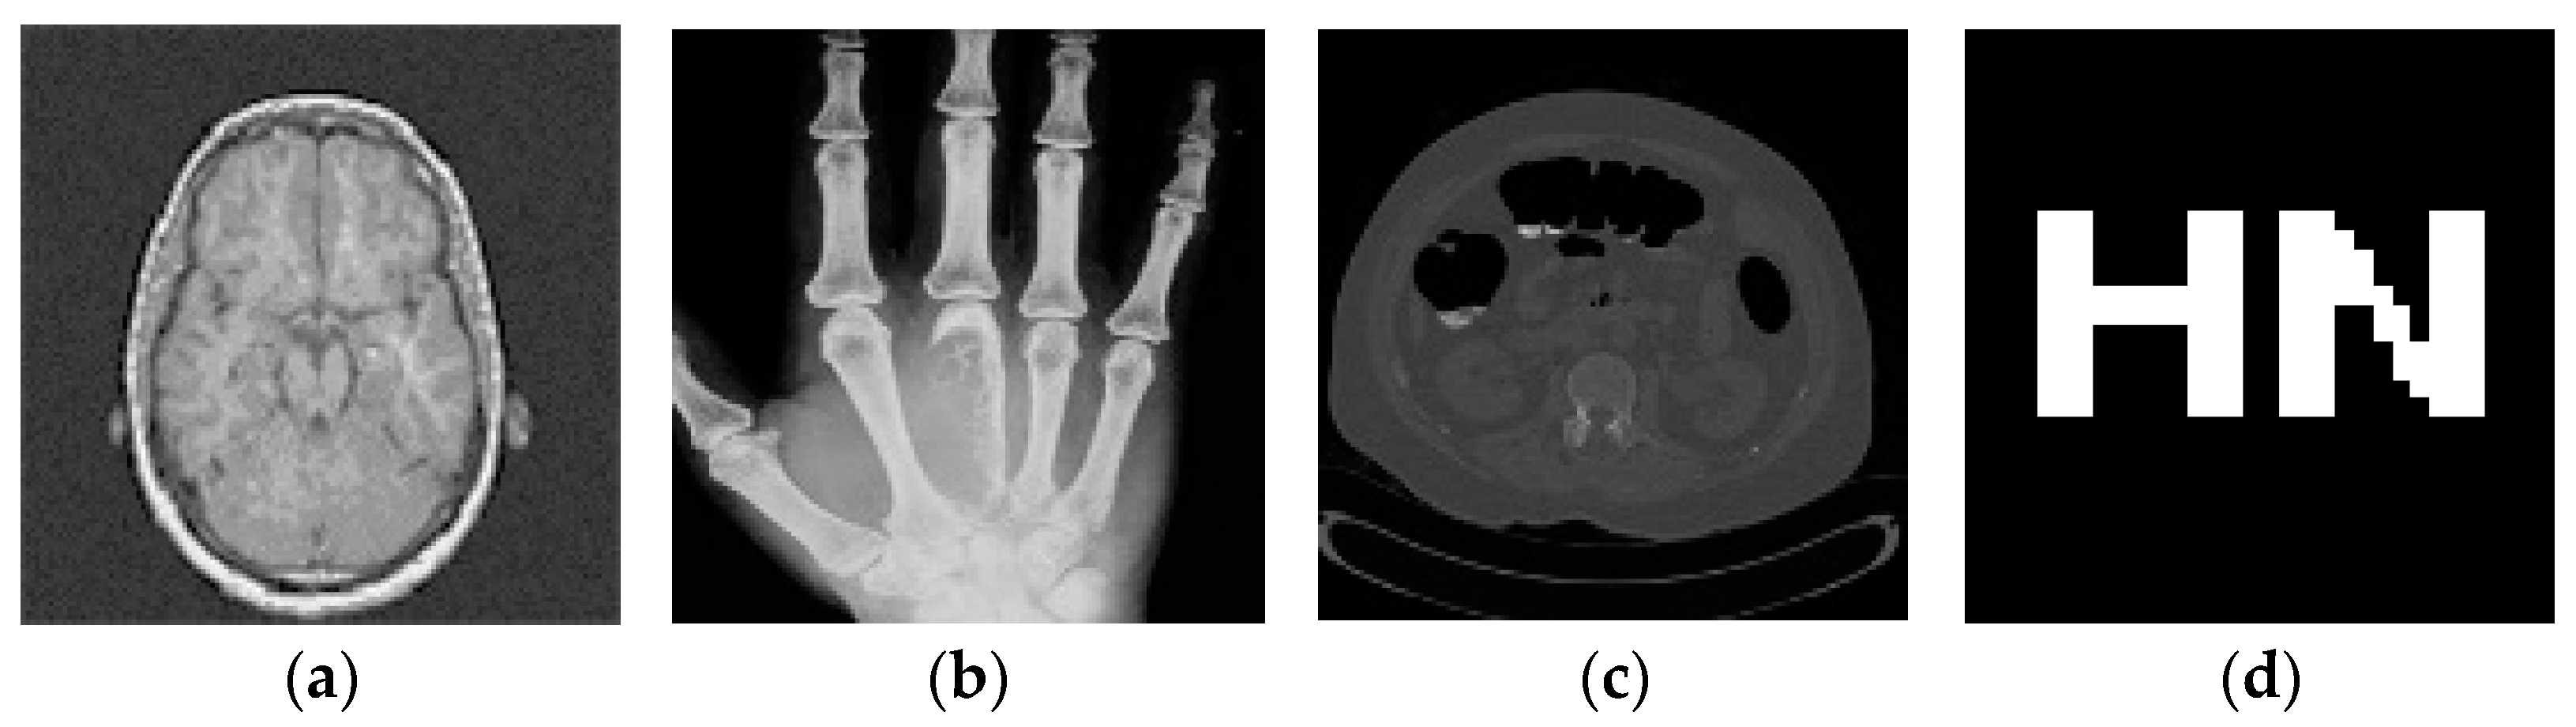

4.1. Testing Different Images